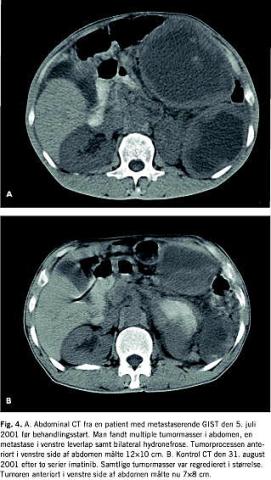

Sygehistorie

En 43-årig mand fik i februar 2001 fjernet en 30 × 35 cm stor cystisk tumor fra fundus ventriculi. Operationen var makro- og mikroskopisk radikal. Patologien viste GIST, og patienten blev henvist til onkologisk afdeling på H:S Rigshospitalet. En kontrol-CT af abdomen i marts 2001 viste normale forhold. Primo juli 2001 blev patienten indlagt akut i dårlig almentilstand med mavesmerter, besværet vandladning og sparsom afføring gennem en uge. Klinisk var der store palpable tumormasser i hele abdomen. CT af abdomen viste multiple tumormasser, heriblandt en tumor anteriort i venstre side af abdomen målende 12 × 10 cm. Der var fri væske i relation til leveren, en metastasesuspekt proces i venstre leverlap samt bilateral hydronefrose (Fig. 4A ). En oversigt over abdomen viste subileus pga. afklemmende tumormasser. Patienten fik anlagt bilaterale nefrostomikatetre og blev den 5. juli 2001 sat i behandling med imatinib 400 mg × 2 dagl. p.o. I løbet af de næste uger blev patientens almentilstand bedre, og han blev smertefri. Ved kontrol CT ultimo august 2001 var levermetastasen samt samtlige cystiske tumormasser i abdomen alle regredieret i størrelse. Tumoren anteriort i venstre side af abdomen målte nu 7 × 8 cm (Fig. 4B ). Bivirkningerne bestod af lette, perifere ødemer, der svandt på diuretisk behandling med Spiron (spironolacton) og Furix (furosid). I september 2001 fik patienten seponeret begge nefrostomikatetre. En CT i november 2001 viste fortsat regression af tumormasserne. I januar 2002 begyndte patienten atter at få tyngdefornemmelse i abdomen. CT af abdomen bekræftede mistanken om progression med vækst af de to største tumorprocesser og tilkomst af betydelige mængder ascites. Behandlingen med imatinib blev seponeret.